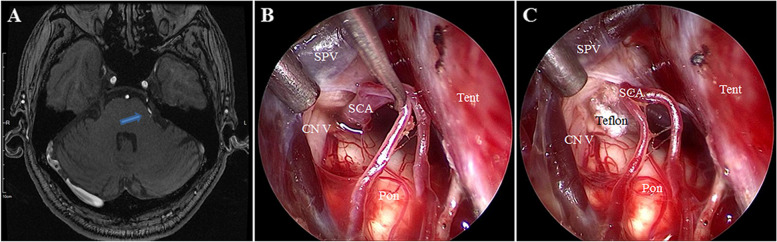

Case presentation: Two patients were presented with severe facial pain and preliminary diagnosis was TN. Preoperative magnetic resonance imaging revealed that a superior cerebellar artery (SCA) compressed the trigeminal nerve in case 1, and a tumor located in the petrous apex extending into the Meckel's cave compressed the trigeminal nerve in case 2. Operations were achieved through the EF-SCITA. The pain was totally relieved with no postsurgical complications in both cases.